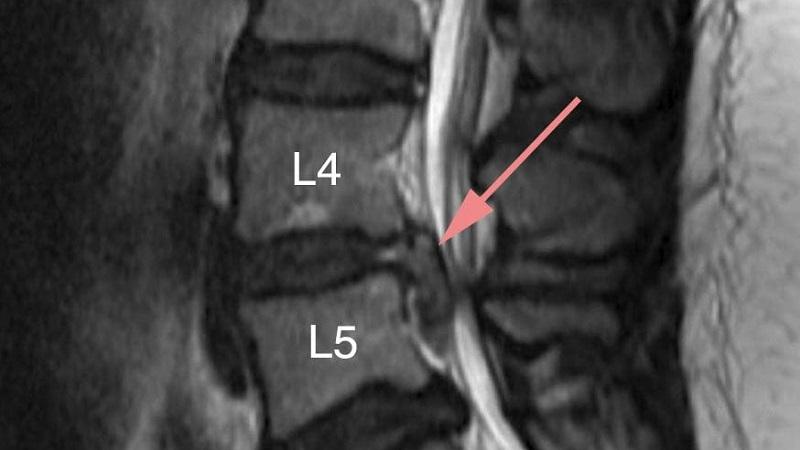

Наиболее часто стеноз спинномозгового канала наблюдается на уровне позвонков L4-L5. В медицинской практике также используется термин «протрузия межпозвоночных дисков». Эта патология представляет опасность, так как может привести к образованию межпозвоночной грыжи. Первым симптомом является интенсивная боль в области этих позвонков.

Размер протрузии диска на уровне L5 может достигать 10 мм. Заболевание может возникнуть в результате травм или неравномерных нагрузок на позвоночник. Лечение стеноза позвоночного канала в поясничной области необходимо начинать как можно скорее, чтобы избежать необходимости в хирургическом вмешательстве.